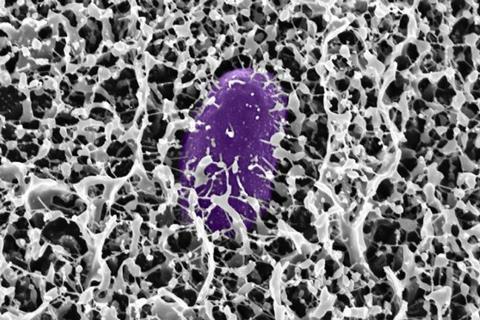

Mucins are bottlebrush-shaped polymers made of complex sugar molecules known as glycans, which are tethered to a peptide backbone. In this study, the researchers discovered that a mucin called MUC2 turns off genes that Salmonella uses to enter and infect host cells.

To infect host cells, Salmonella must produce proteins that are part of the type 3 secretion system (T3SS), which helps bacteria form needle-like complexes that transfer bacterial proteins directly into host cells. These proteins are all encoded on a segment of DNA called Salmonella pathogenicity island 1 (SPI-1).

The researchers found that when they exposed Salmonella to a mucin called MUC2, which is found in the intestines, the bacteria stopped producing the proteins encoded by SPI-1, and they were no longer able to infect cells.